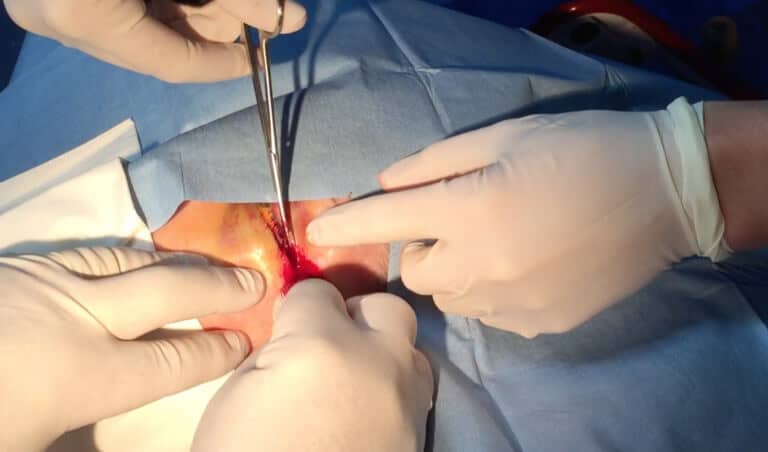

The Procedure

The procedure itself is relatively simple and is shown below in a video:

- Advise the patient and of what is to be done and get consent.

- Give gentle sedation. Our patient received 1mg IV midazolam, which was adequate

- Clean the area around the eye

- Inject 1-2ml of 1% lignocaine with adrenaline into the lateral canthus. Do not damage the globe

- Devascularise the Lateral Canthus: Use a small clamp to clamp the tissues for about 15-30 seconds.

- Make an Incision into the lateral canthus- staying away from the globe.

- Next cut the canthal tendons. These run superiorly and inferiorly and feel like guitar strings. Usually one tendon only needs to be cut. In the example above in the video, the ophthalmologist wanted both cut.

There may be some bleeding, however this is easily controlled by direct pressure. The eye pressure should reduce almost immediately.

In our patient the eye pressure was measured within 5 minutes and had dropped to 29mmHg and then continued to drop further. The patient also had medical management including Diamox 250 qid and timolol eye drops.